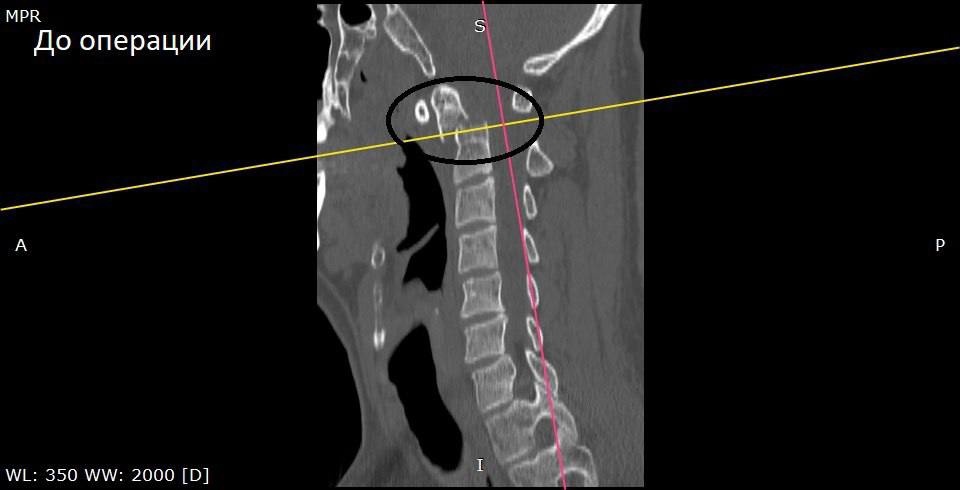

Местного жителя «скорая» доставила в приемное отделение Воронежской городской клинической больницы скорой медицинской помощи №1. Врачи выявили перелом второго шейного позвонка со смещением отломка.

«Учитывая нестабильность перелома и необходимость стабилизации отломков для предотвращения развития тяжелых неврологических нарушений вплоть до летального исхода, выполнено оперативное вмешательство — окципитоспондилодез», – рассказали в больнице.